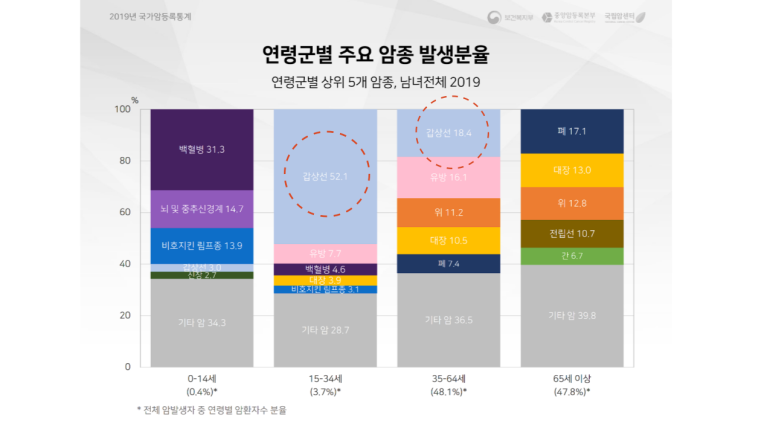

다른 암종과 비교하면 갑상선암은 15~64세의 젊은 분들에게 주로 발생하는 것도 볼 수 있습니다.